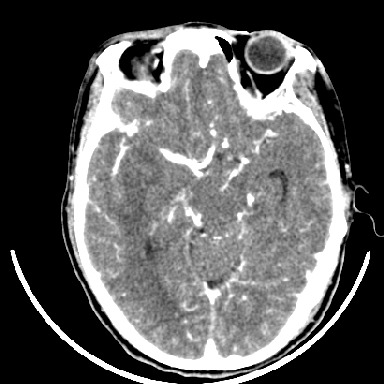

标题: CT6056:脑出血(血管畸形?) [打印本页]

标题: CT6056:脑出血(血管畸形?)

m 40突发头痛左侧偏瘫3小时

考虑高血压性脑出血,依据:

1是高血压性脑出血的好发部位,形态呈肾形,是高血压性脑出血的常见形状

2增强时占位效应加重了,考虑出血还没有停止

3病灶周围水肿不是太厉害,一般肿瘤出血水肿多非常明显

4病灶周围的‘软组织’影没有明显的强化

5至于脑血管畸形引起的出血,暂时没有看到明显的畸形血管影,也不太支持

另附部分资料:“血液溢出血管外形成血肿,其内含有大量血红蛋白、血浆白蛋白,球蛋白,因这些蛋白对x线的吸收系数高于脑质,故ct呈现高密度阴影,ct值达40~90h,最初高密度灶呈非均匀一致性,中心密度更高,新鲜出血灶边缘不清。基底节区血肿多为“肾”型,内侧凹陷,外侧膨隆,因外侧裂阻力较小,故向外凸,其它部位血肿多呈尖圆形或不规则形”

术中抽出40ml陈旧血液,血肿底部似见一条索血管影